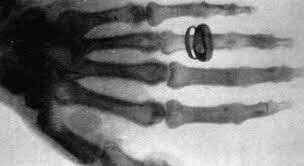

• Unidad móvil de Rayos X

Unidad móvil de Rayos X

En 1895 se descubrió que con un un cartón envuelto de platinocianuro los colores se volvían fluorescentes. Esta hazaña se le debe a los científicos Hittorff y Crookers